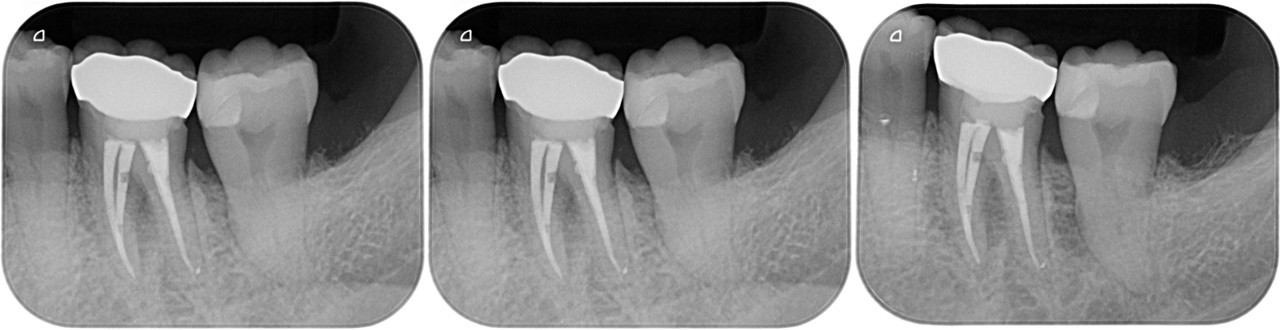

左:2021.08.27 中:2021.08.27 右:2022.03.23